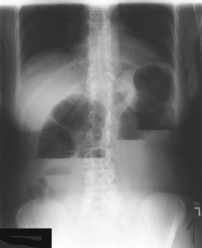

The air-barium distribution within the stomach and large intestine changes with various body positions. By knowing these distribution patterns, one can determine in which body position a radiograph was taken. Air always rises to the highest levels, and the heavy barium settles to the lowest levels (air is black, barium is white).

The ascending and descending portions are located more posteriorly, and thus more of these parts in general would be filled with barium (white) in the supine position and with air (black) in the prone position.

This much separation of barium and air occurs generally only with double-contrast barium-air studies.

Air-fluid levels would be seen in the erect position in which the air would rise to the highest position in each of the various sections of the large intestine, as shown in the accompanying figure.

Right and left decubitus projections (not shown on these drawings) also would demonstrate air-fluid levels, with air again rising to the highest portions.